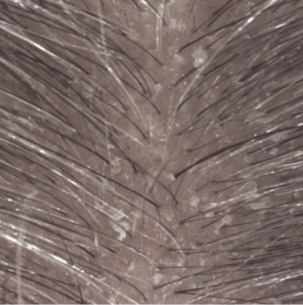

Lo shampoo KERTYOL PSO è specialmente indicato per la cura del cuoio capelluto soggetto a psoriasi.

La sua formula innovativa agisce a tutti i livelli della fisiopatologia della psoriasi. Lo shampoo trattante può essere utilizzato in associazione a trattamenti dermatologici specifici, in alternanza o come mantenimento per limitare la ricomparsa delle placche.

Risultati di efficacia

Spessore delle placche dopo 1 mese (3)